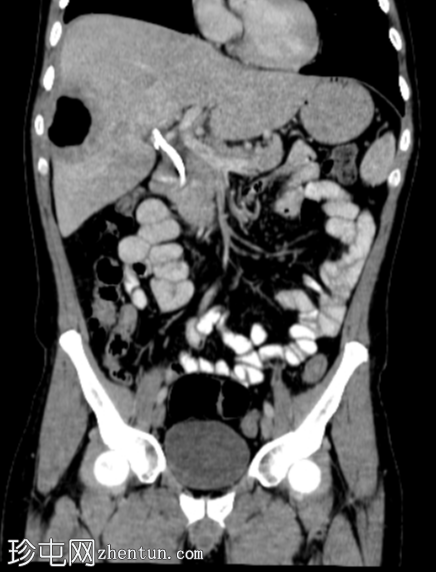

2.png

平扫

平扫图像显示胆囊切除夹、胆道积气、胆总管支架及右肝叶VIII段囊性病变伴气液平面。